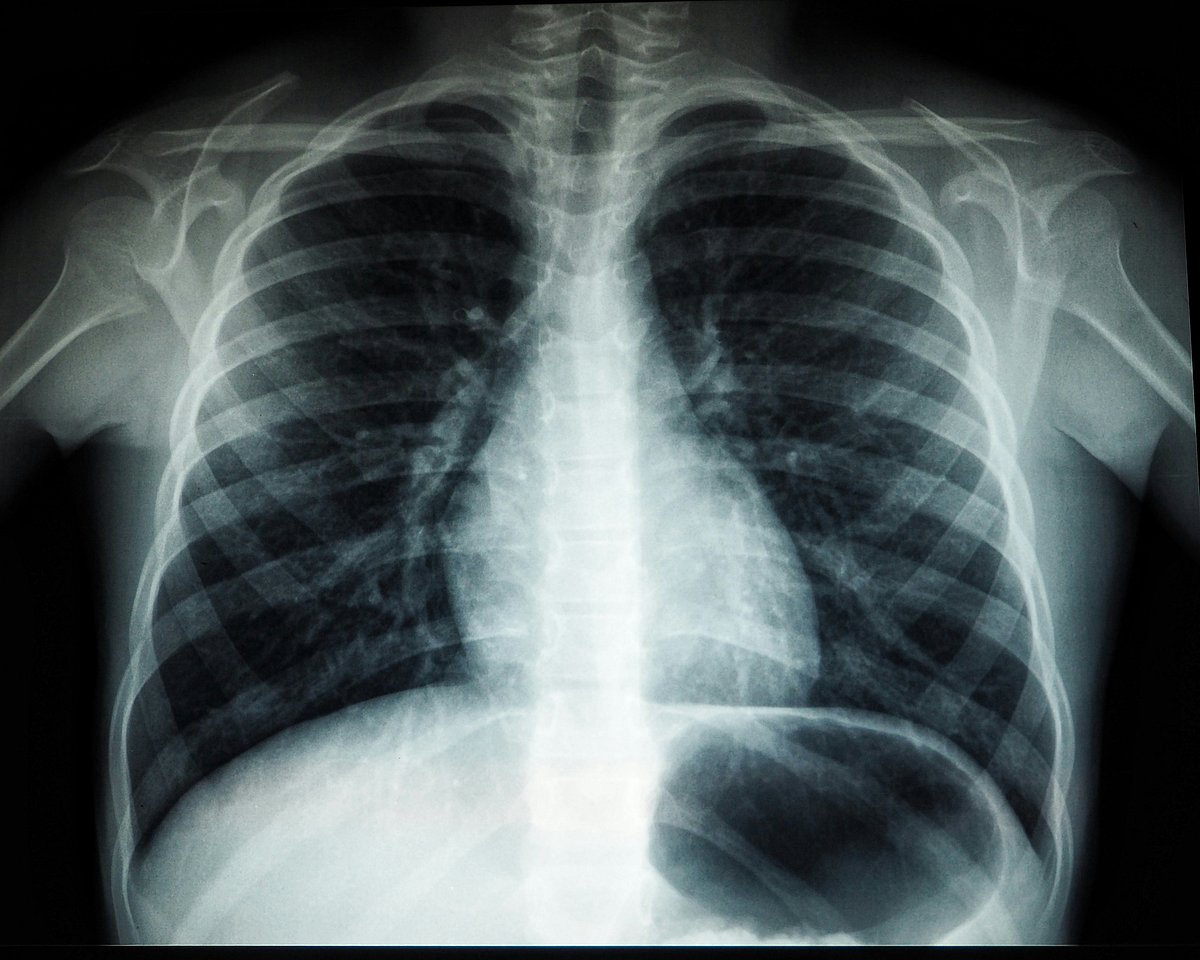

Deadlier Than HIV Or Malaria: TB Stays India's Top Infectious Killer, Says Study

In contrast to other illnesses such as cancer, and cardiovascular diseases which are more frequent in older populations, TB affects the young.